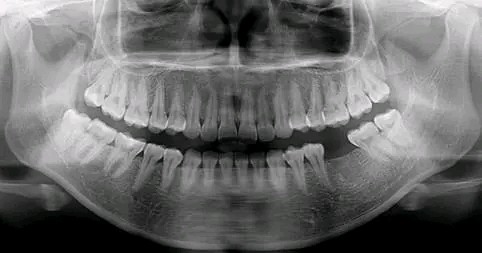

不拍片根本不知道你的牙齿长得会有多奇葩!

X线片一般分为全景片(也就是曲面断层)和根尖片,有些特殊的情况还需要拍CT,具体需要拍哪种片子,一般根据每个人的牙齿情况不同会有区别。

全景片